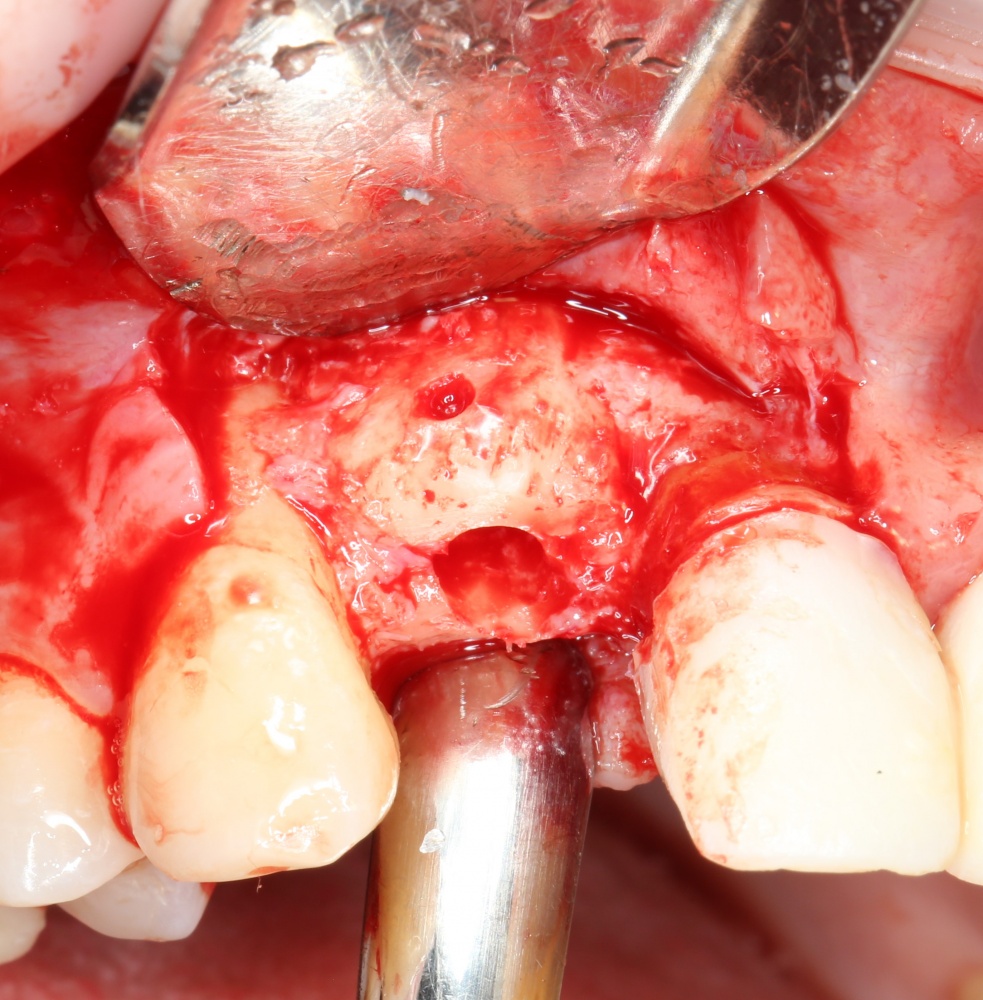

Кстати, обрати внимание на ширину альвеолярного гребня (левая картинка). Она чуть меньше 3 мм. Это объясняет, почему я засомневался в возможности установки имплантатов одновременно с остеопластикой. Понятно и без КЛКТ.

Наперво, мне нужно удалить разрушенный зуб и получить костный аутотрансплантат.

Возвращаемся к основной операционной области. Еще раз посмотрим на альвеолярный гребень, поофигеваем от его ширины и моих грандиозных планов: